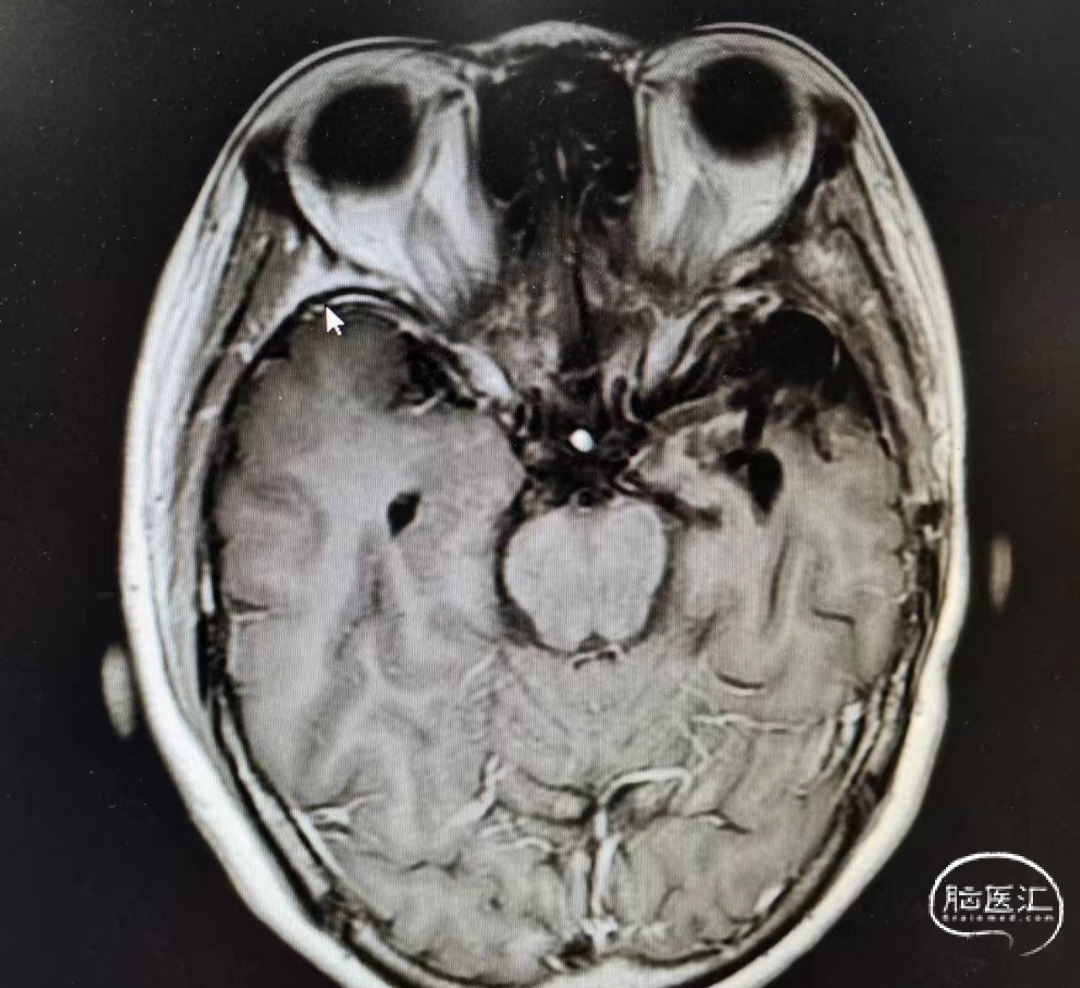

图:一次术后的MRI